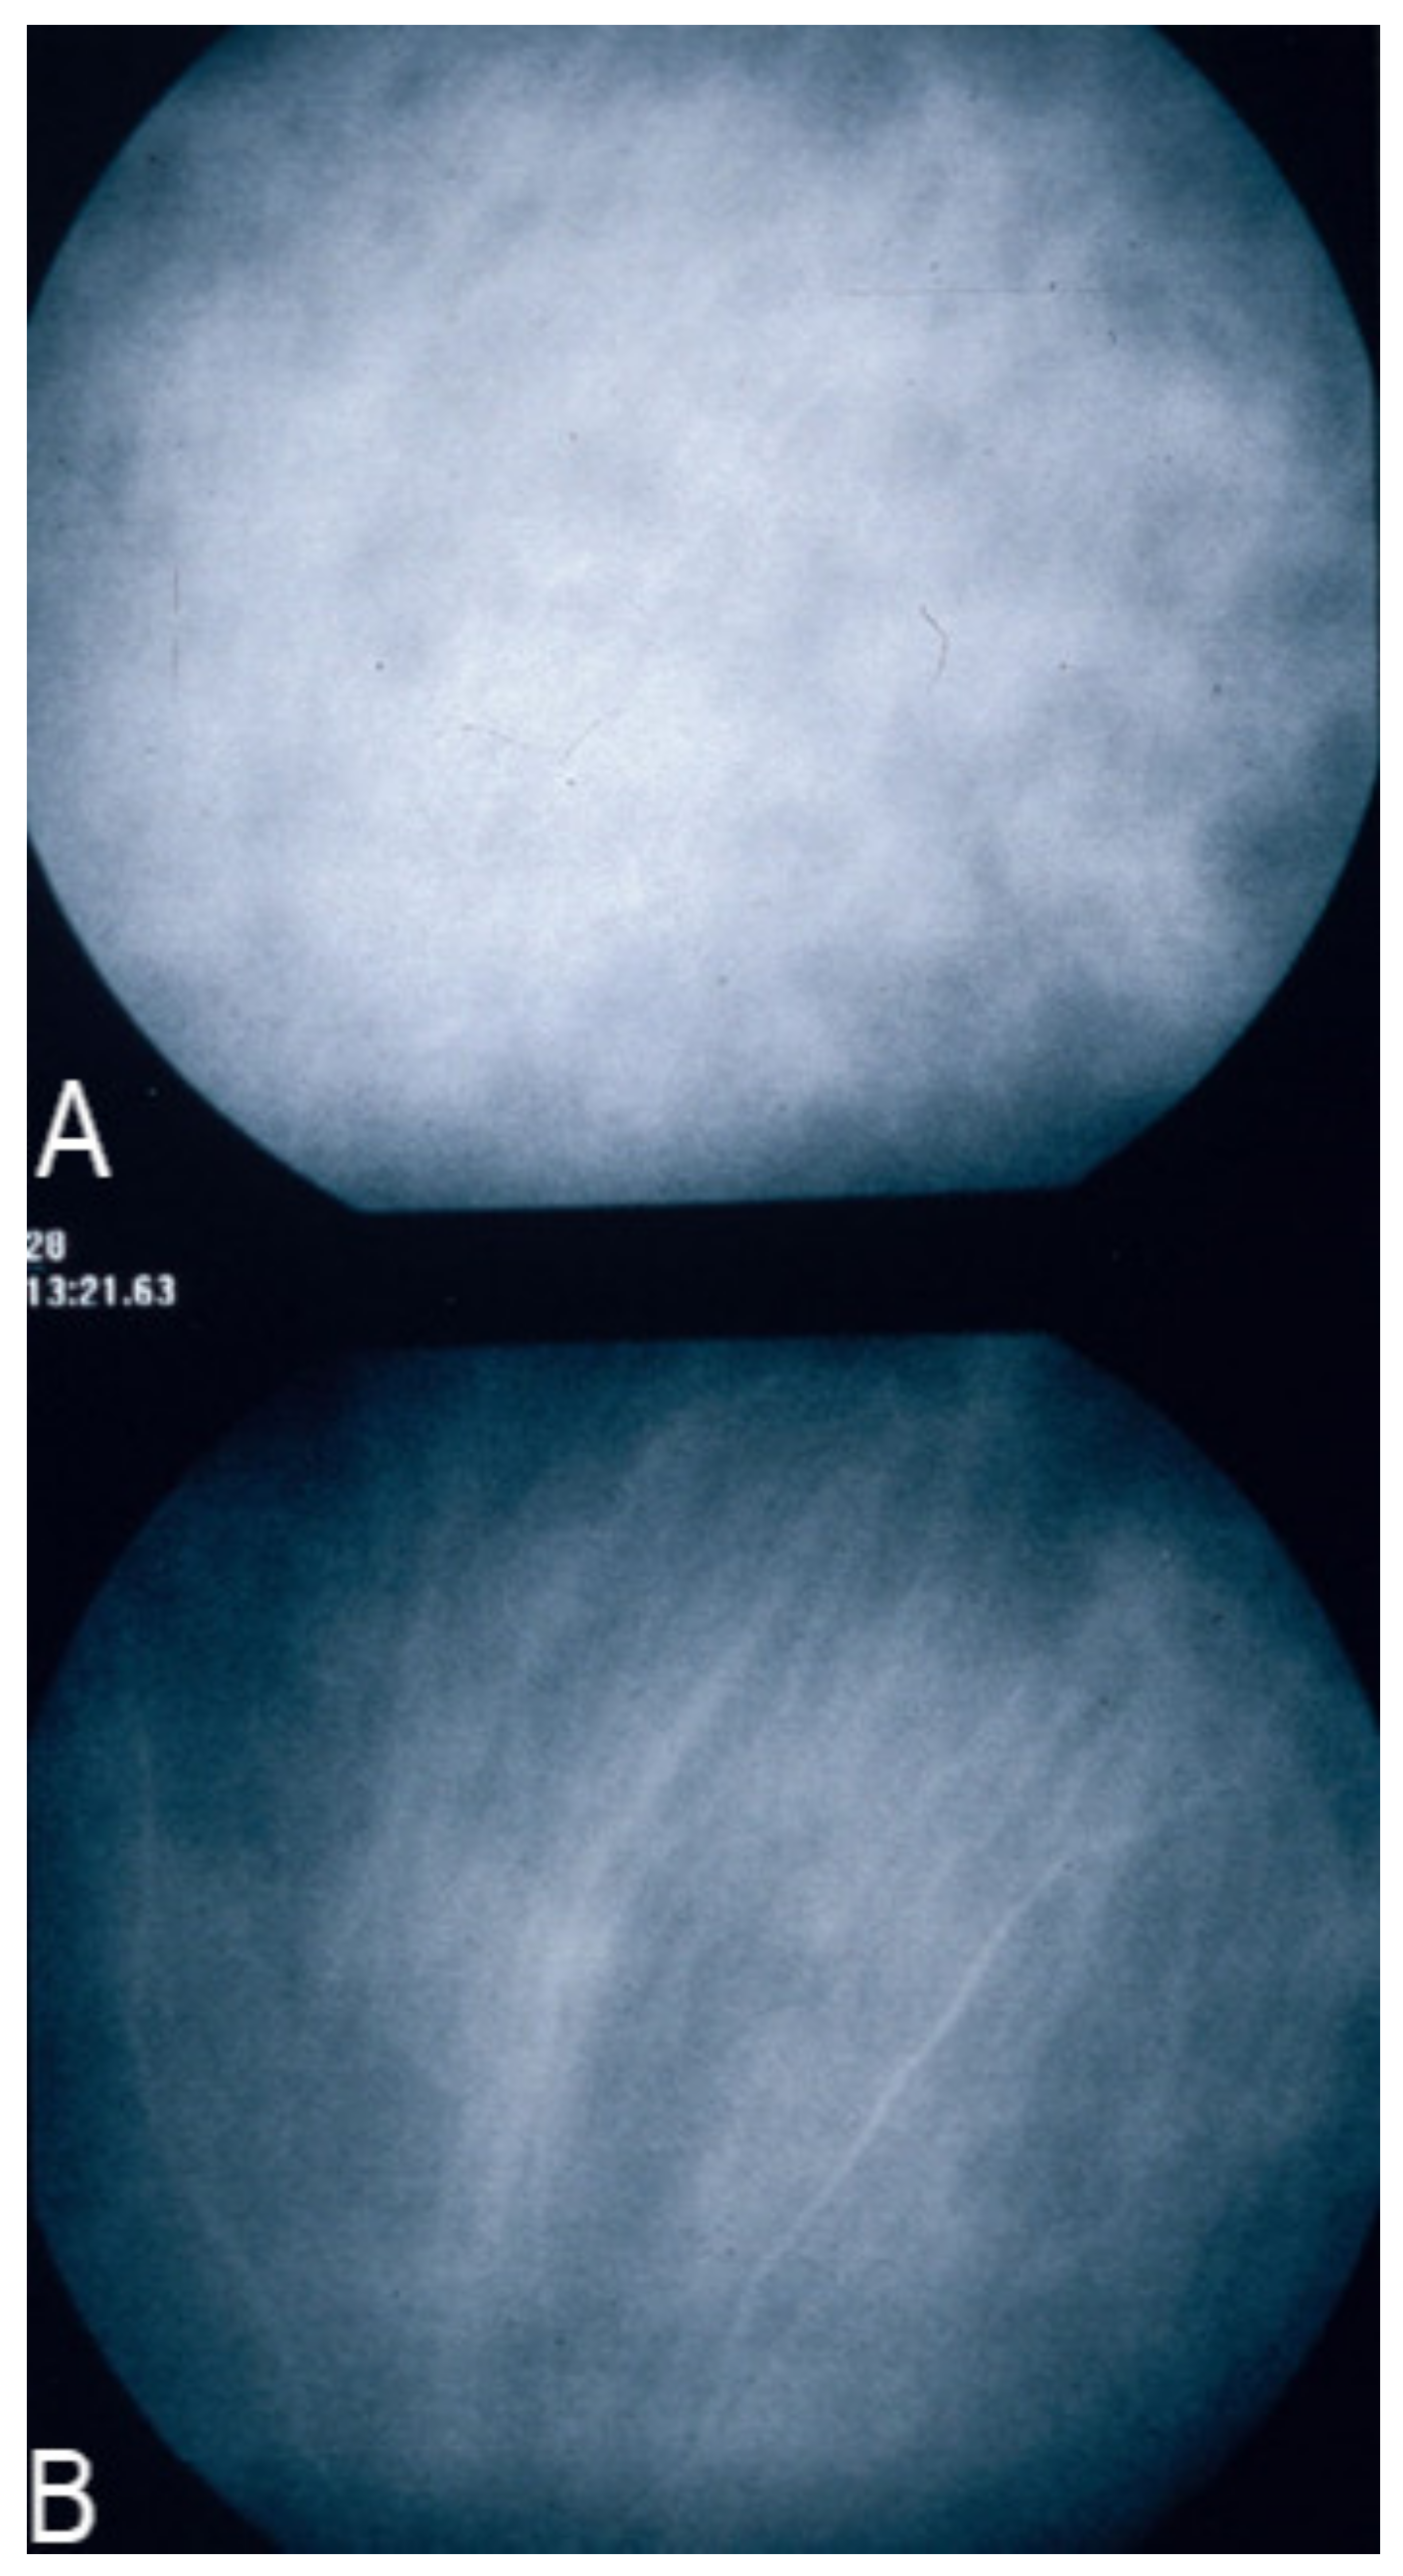

(1) Inflammatory choriocapillaris non-perfusion or hypoperfusion, represented on the Figure 3A appears as irregular geographic areas of hypofluorescence or absence of fluorescence (Figure 4). This pattern is found in primary or secondary choriocapillaritis or inflammatory choriocapillaropathies.

Figure 4.

Indocyanine green angiography (ICGA), type 1 pattern: choriocapillaris non-perfusion. Typical geographic areas of dark non-fluorescence in case of acute posterior multifocal placoid pigment epitheliopathy or acute multifocal ischaemic choriocapillaritis (APMPPE/AMIC).